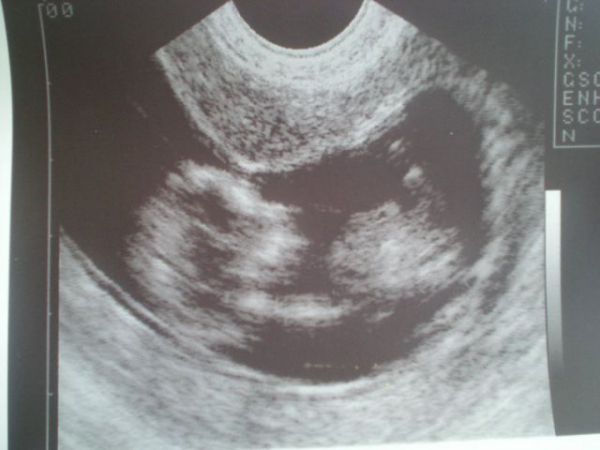

Tak tady jdeme nejlépe vidět, další fotku máme tak trochu na nic od mého minulého dr. ale v pátek jedeme na velký, tak snad pořídíme lepší :)